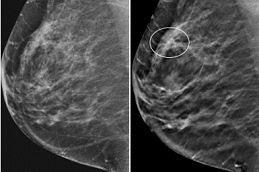

Breast Cancer Screening is a low-impact, preventive testing approach formulated to identify the breast-associated abnormalities in early stages to prevent them from getting worse, thus promoting breast health.

If screening is conducted by employing the latest 3D mammography or MRI, it appears to be usually pricey as compared to standard mammograms.